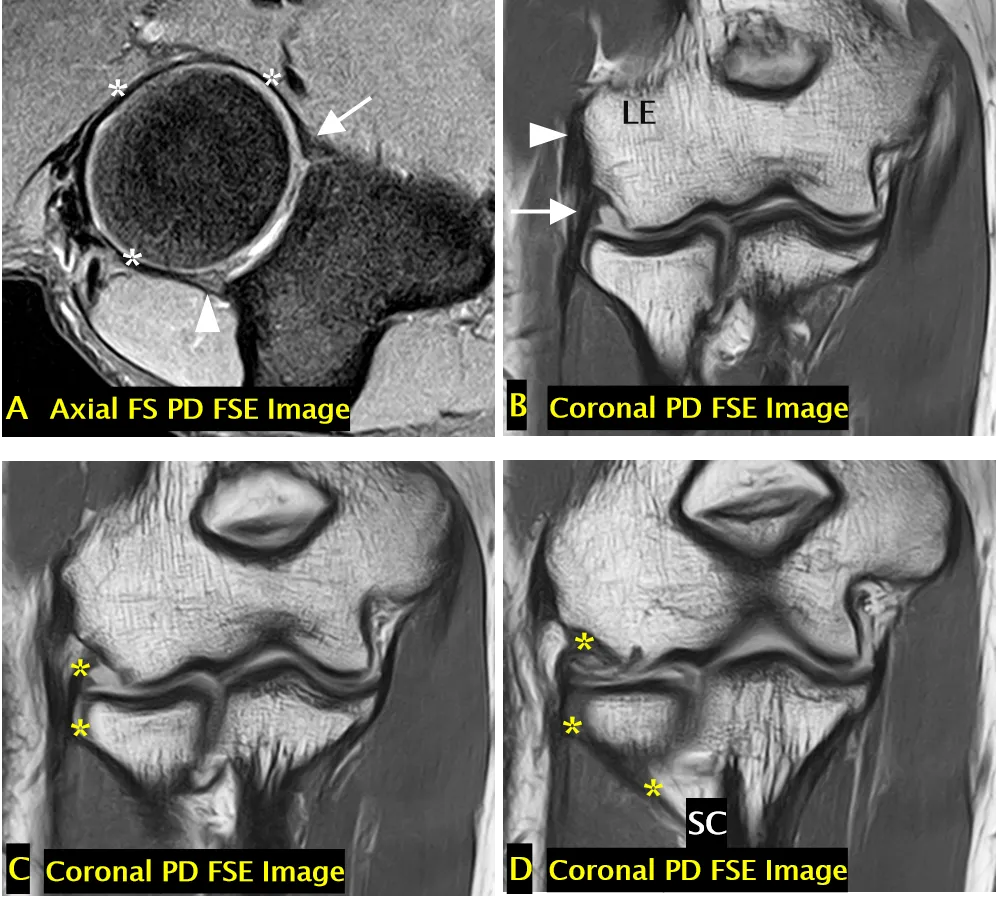

外侧副韧带复合体

A 图:完整的环状韧带,起自并止于尺骨半月切迹(分别用箭头和箭头头标注),环状韧带环绕桡骨头外周(* 标注)。B-D 图:完整的外侧尺侧副韧带(C、D 中 * 标注)和桡侧副韧带(B 中箭头标注);外侧尺侧副韧带从外上髁(LE 标注)延伸至尺骨的旋后肌嵴(SC 标注);桡侧副韧带从外上髁延伸至环状韧带;外侧尺侧副韧带环绕桡骨颈后方;桡侧副韧带位于外侧尺侧副韧带前方;可见共同伸肌肌腱(B 中箭头头标注)。